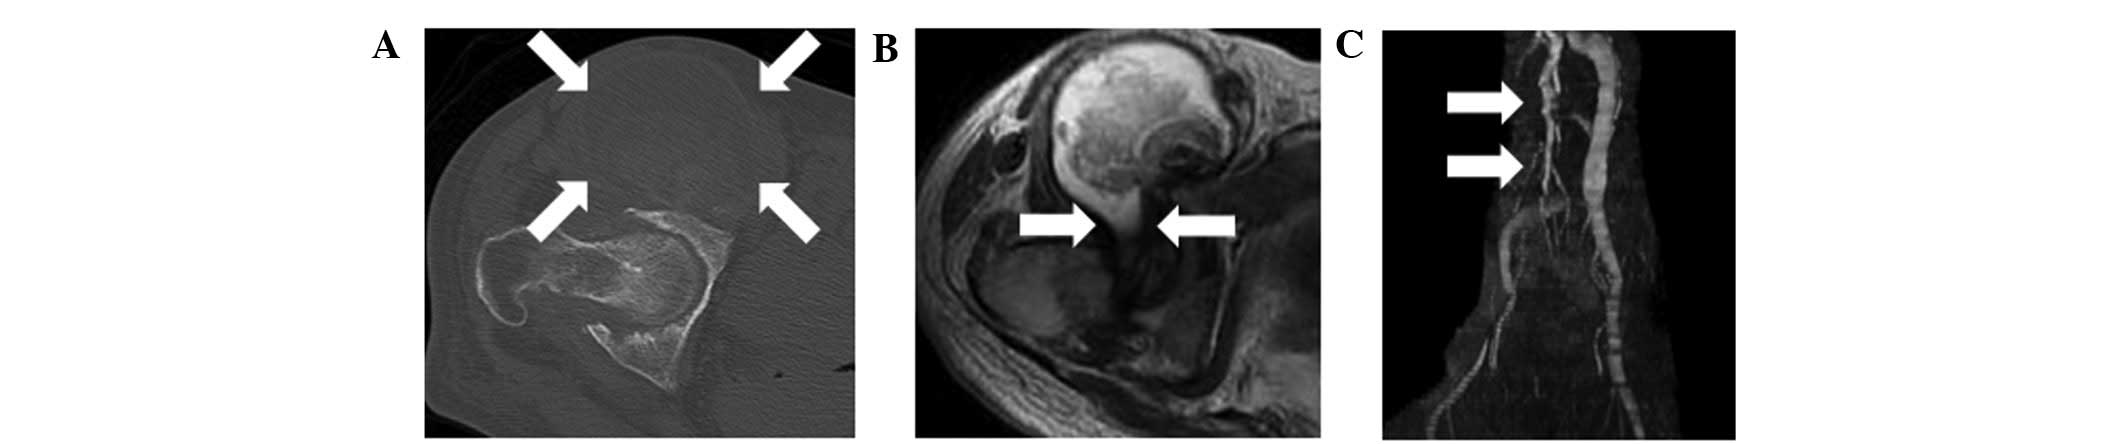

Plain radiographs showed destruction of the right hip and collapse of the right femoral head. Computed tomography (CT) showed joint space narrowing and an enlarged mass anterior to the right hip joint (Fig. 1A). Magnetic resonance imaging (MRI) showed an enlarged mass anterior to the right hip joint. The mass displaced the iliopsoas muscle laterally, and was shown to connect with the joint space of the right hip (Fig. 1B). The signal intensity of the lesion was abnormal on T1- and T2-weighted images. An MRI venography showed that the femoral vein was displaced medially by the mass (Fig. 1C). Needle aspiration yielded 110 ml of black-brown fluid. The cytology and culture results were negative. The diagnosis of iliopectineal bursitis associated with destruction of a rheumatoid hip joint was made on the basis of these findings, and surgery was thus performed.

Figure 1.

(A) Computed tomography (CT) showed an enlarged mass anterior to the right hip joint (white arrow). (B) Magnetic resonance imaging (MRI) showing an enlarged mass anterior to the right hip joint. An axial T2-weighted MRI image showed that there was a connection between the mass and the right hip joint (white arrow). (C) MRI venography demonstrated that the right femoral vein was displaced medially by the mass (white arrow).